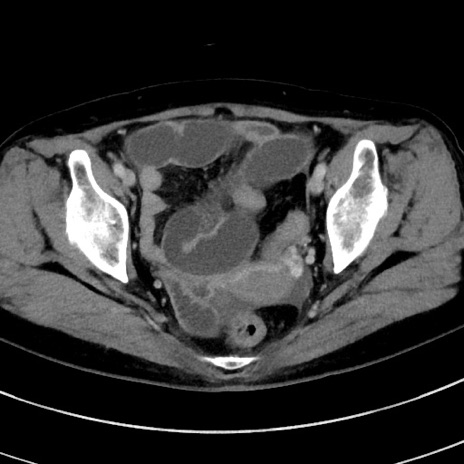

症例9(横断像)

【症例】 60歳代女性

【主訴】むかつき、みぞおちの痛み

【現病歴】3日前よりむかつきがあり、食事がとれない。

【既往歴】糖尿病

【身体所見】発熱なし、心窩部圧痛軽度あるも、腹膜刺激症状なし。

【データ】WBC 7400、CRP 1.92